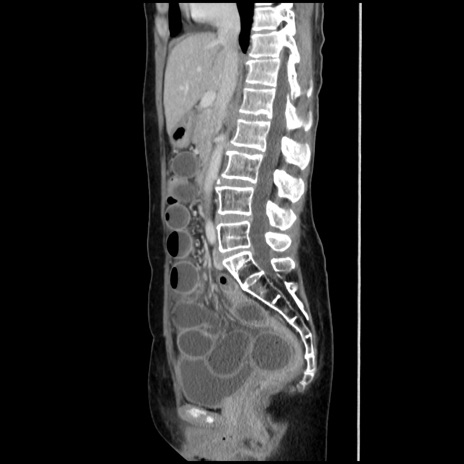

【症例】40歳代 女性

【主訴】上腹部痛、嘔気・嘔吐

【現病歴】約9時間前頃から急に上腹部痛、嘔気、嘔吐が出現。改善しないため救急要請。

【既往歴】子宮頚癌(広汎子宮全摘術、放射線療法)、腸閉塞

【身体所見】腹部:平坦、軟、腸雑音亢進、上腹部を中心に腹部全体に圧痛あり。

【データ】WBC 8400、CRP 0.03

横断像